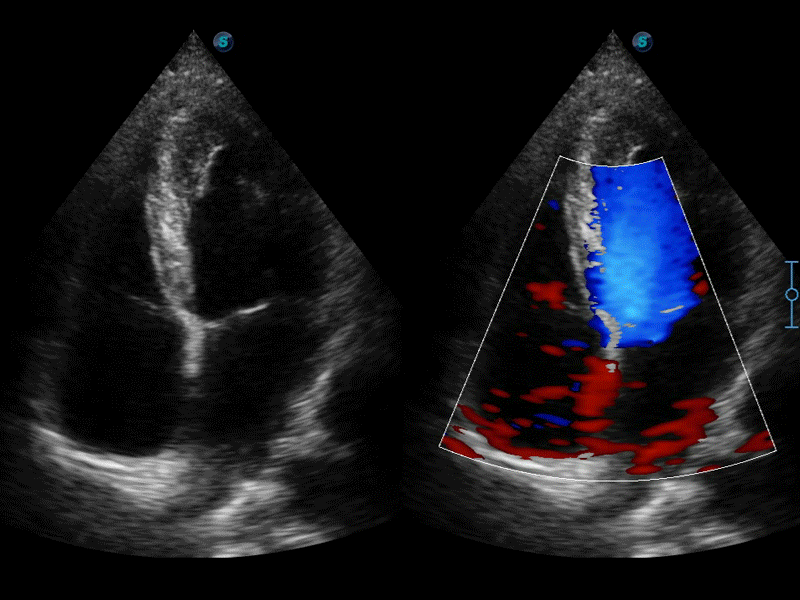

高分辨率血流成像技術(shù)提高了對(duì)低速血流信號(hào)的檢測(cè)能力。在提高空間分辨率的同時(shí),也克服了血流外溢現(xiàn)象,為用戶提供更加真實(shí)的血流動(dòng)力學(xué)信息。

自動(dòng)識(shí)別收縮和舒張末期心肌內(nèi)膜,自動(dòng)計(jì)算射血分?jǐn)?shù)EF值。